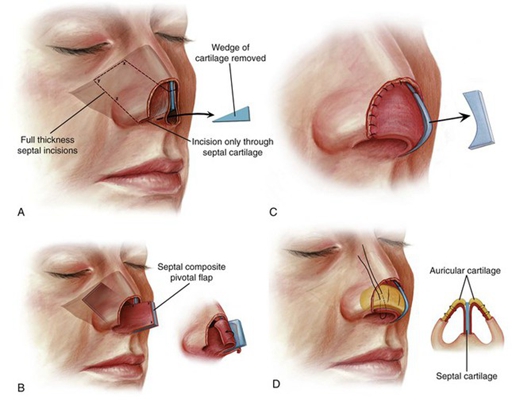

鼻中隔彎曲手術圖解 (7)

鼻中隔彎曲手術圖解 (8)

鼻中隔彎曲手術圖解 (9)